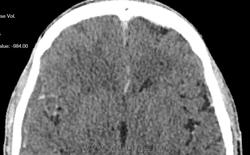

- определяется участок пониженной плотности в полюсно-базальных отделах правой лобной доли (+25+30Hu), являющийся зоной энцефалита, без четких контуров, не накапливающий контрастный препарат при контрастном усилении.

Обратите внимание на субдуральное пространство справа. Определяется тонкое пластинчатое скопление патологического изоденсного содержимого над конвекситальными отделми правой гемисферы большого мозга. Слева оболочечные пространства выражены обычно.

Каюсь, я так сосредоточилась на костных изменениях, что факт наличия этого содержимого в третьем часу ночи был мной упущен.